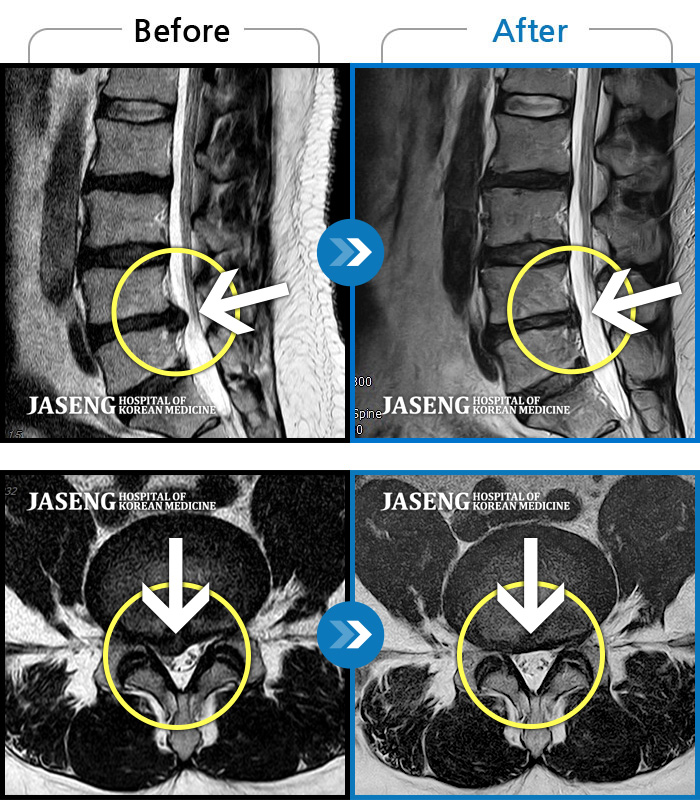

허리디스크

도움받은 사례

강남 · 강만호 원장

허리통증이 심해서 숙이기 어렵고 차에서 내리기 힘들었습니다.

촬영시기

2021.01.06 ~ 2025.03.10

2025.03.20